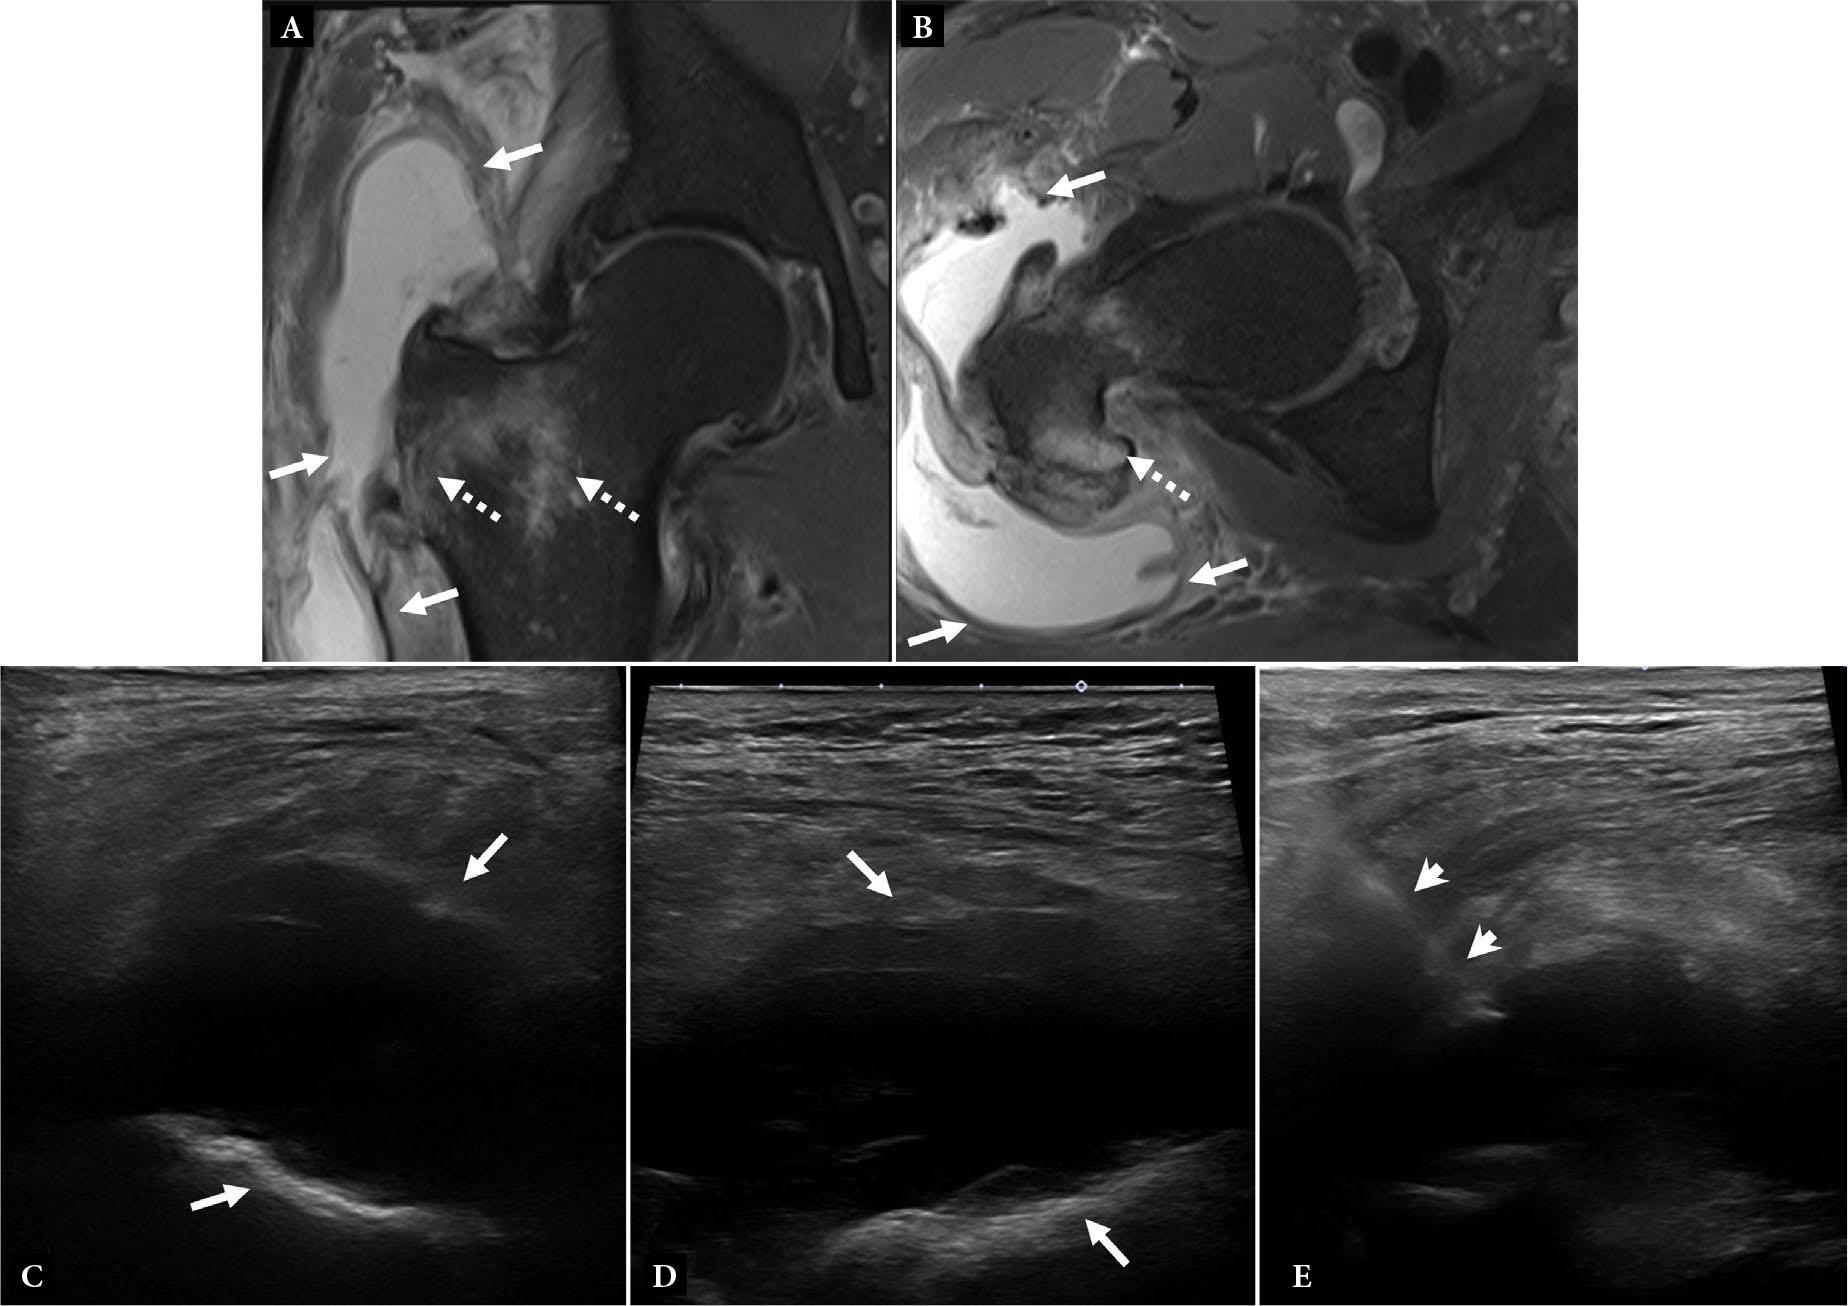

Fig. 4.